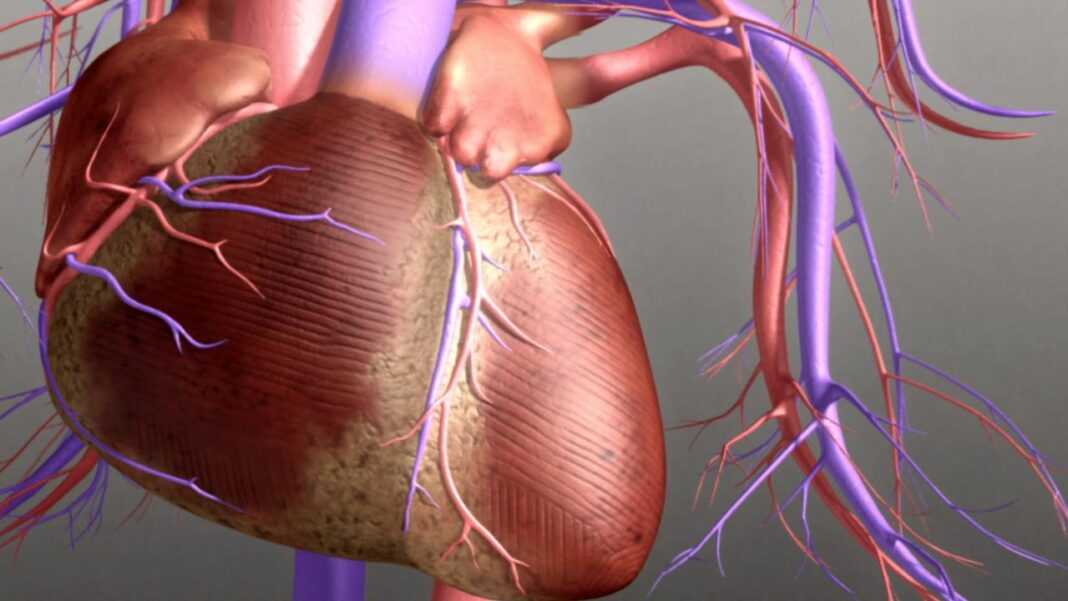

«Αυτά τα ευρήματα υπογραμμίζουν τη σημασία της πρόληψης του καπνίσματος κατά πρώτο λόγο, ειδικά μεταξύ των παιδιών και των νεαρών ενηλίκων». λέει ο ανώτερος συγγραφέας της μελέτης Kunihiro Matsushita, MD, Ph.D., αναπληρωτής καθηγητής στο Τμήμα Επιδημιολογίας της Σχολής Bloomberg. «Ελπίζουμε τα αποτελέσματά μας να ενθαρρύνουν τους σημερινούς καπνιστές να το κόψουν, καθώς η βλάβη του καπνίσματος μπορεί να διαρκέσει έως και τρεις δεκαετίες». Η καρδιακή ανεπάρκεια είναι μια προοδευτική κατάσταση κατά την οποία η καρδιά χάνει την ικανότητά της να αντλεί αρκετό αίμα για να καλύψει τις ανάγκες του σώματος. Είναι μια από τις πιο κοινές αιτίες αναπηρίας και θανάτου στις ανεπτυγμένες χώρες, με περισσότερους από 6 εκατομμύρια ενήλικες να ζουν με καρδιακή ανεπάρκεια στις Η.Π.Α., σύμφωνα με τα πιο πρόσφατα στοιχεία του Κέντρου Ελέγχου και Πρόληψης Νοσημάτων. Εκτός από το κάπνισμα, οι παράγοντες κινδύνου για καρδιακή ανεπάρκεια περιλαμβάνουν την παχυσαρκία, την υπέρταση, τον διαβήτη, τη στεφανιαία νόσο και την προχωρημένη ηλικία.

Υπάρχουν δύο τύποι καρδιακής ανεπάρκειας: μειωμένο κλάσμα εξώθησης και διατηρημένο κλάσμα εξώθησης. Σε καρδιακή ανεπάρκεια με μειωμένο κλάσμα εξώθησης, η αριστερή κοιλία – η κύρια καρδιακή αντλία – αποτυγχάνει να συστέλλεται επαρκώς όταν αντλεί αίμα προς τα έξω. Η καρδιακή ανεπάρκεια με μειωμένο κλάσμα εξώθησης συνδέεται πιο στενά με τη στεφανιαία νόσο. Η θεραπεία περιλαμβάνει διάφορα φάρμακα που βελτιώνουν την πρόγνωση. Σε καρδιακή ανεπάρκεια με διατηρημένο κλάσμα εξώθησης, η αριστερή κοιλία αποτυγχάνει να χαλαρώσει επαρκώς μετά τη σύσπαση. Η θεραπεία για την καρδιακή ανεπάρκεια με διατηρημένο κλάσμα εξώθησης είναι πολύ περιορισμένη, γεγονός που καθιστά την πρόληψή της εξαιρετικά σημαντική. Ταυτόχρονα, οι παράγοντες κινδύνου είναι λιγότερο σαφείς. Προηγούμενες μελέτες έχουν συνδέσει το κάπνισμα με υψηλότερο κίνδυνο διατήρησης του κλάσματος εξώθησης, ενώ άλλες όχι.